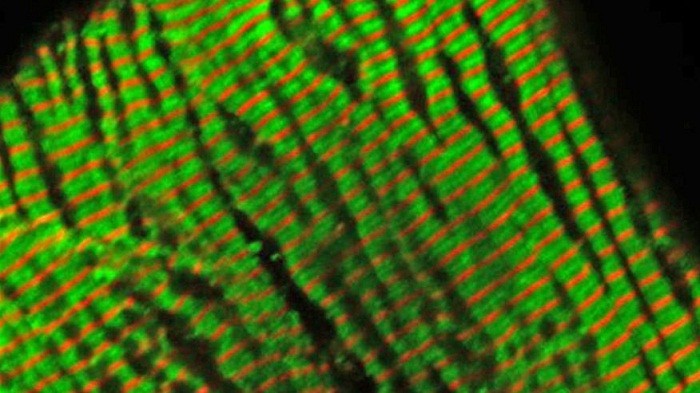

Study authors analyzed the relationship between how sarcomeres generate tension and differences in calcium cycling. These two factors are altered in cardiomyopathy patients, and studying this effect can give doctors insight on how quickly the heart will evolve as disease progresses, Molkentin said.

Using normal mice, plus mice genetically engineered to have gene mutations associated with various cardiomyopathies, researchers analyzed calcium cycling rates and muscle tension generation. Next, integrating the overall tension produced by isolated cardiomyocytes, researchers came up with an algorithm that successfully predicted whether the mice would develop HCM or DCM.